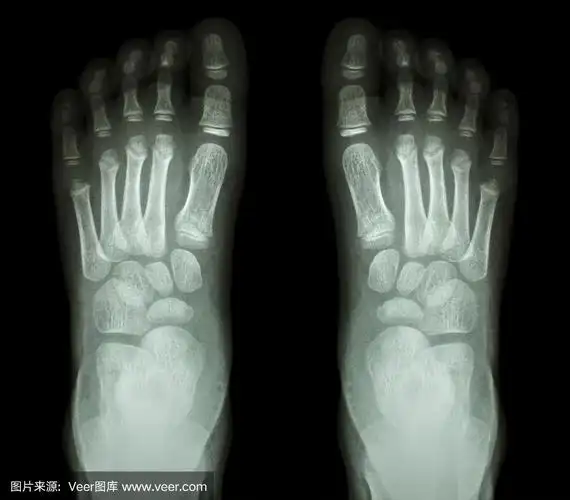

x光检查正常儿童脚部

正常脚的 x 射线图像两个 sid